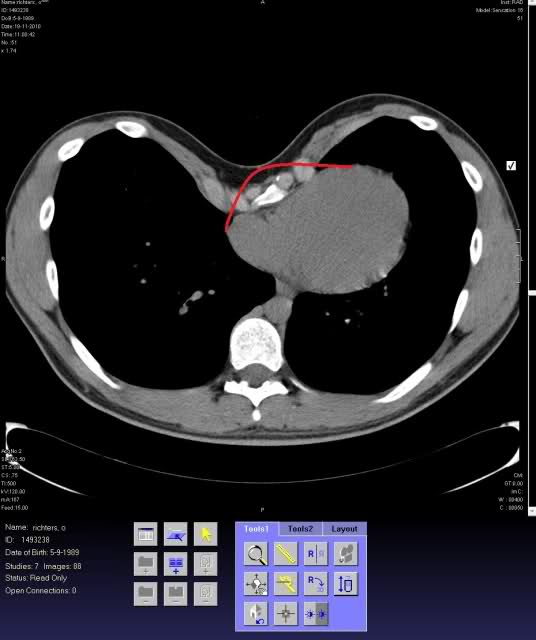

daarnaast heb ik ook een Pectus Excavatus, altijd wel aan geirriteerd en nu zie ik ook dat het gevolgen kan hebben!